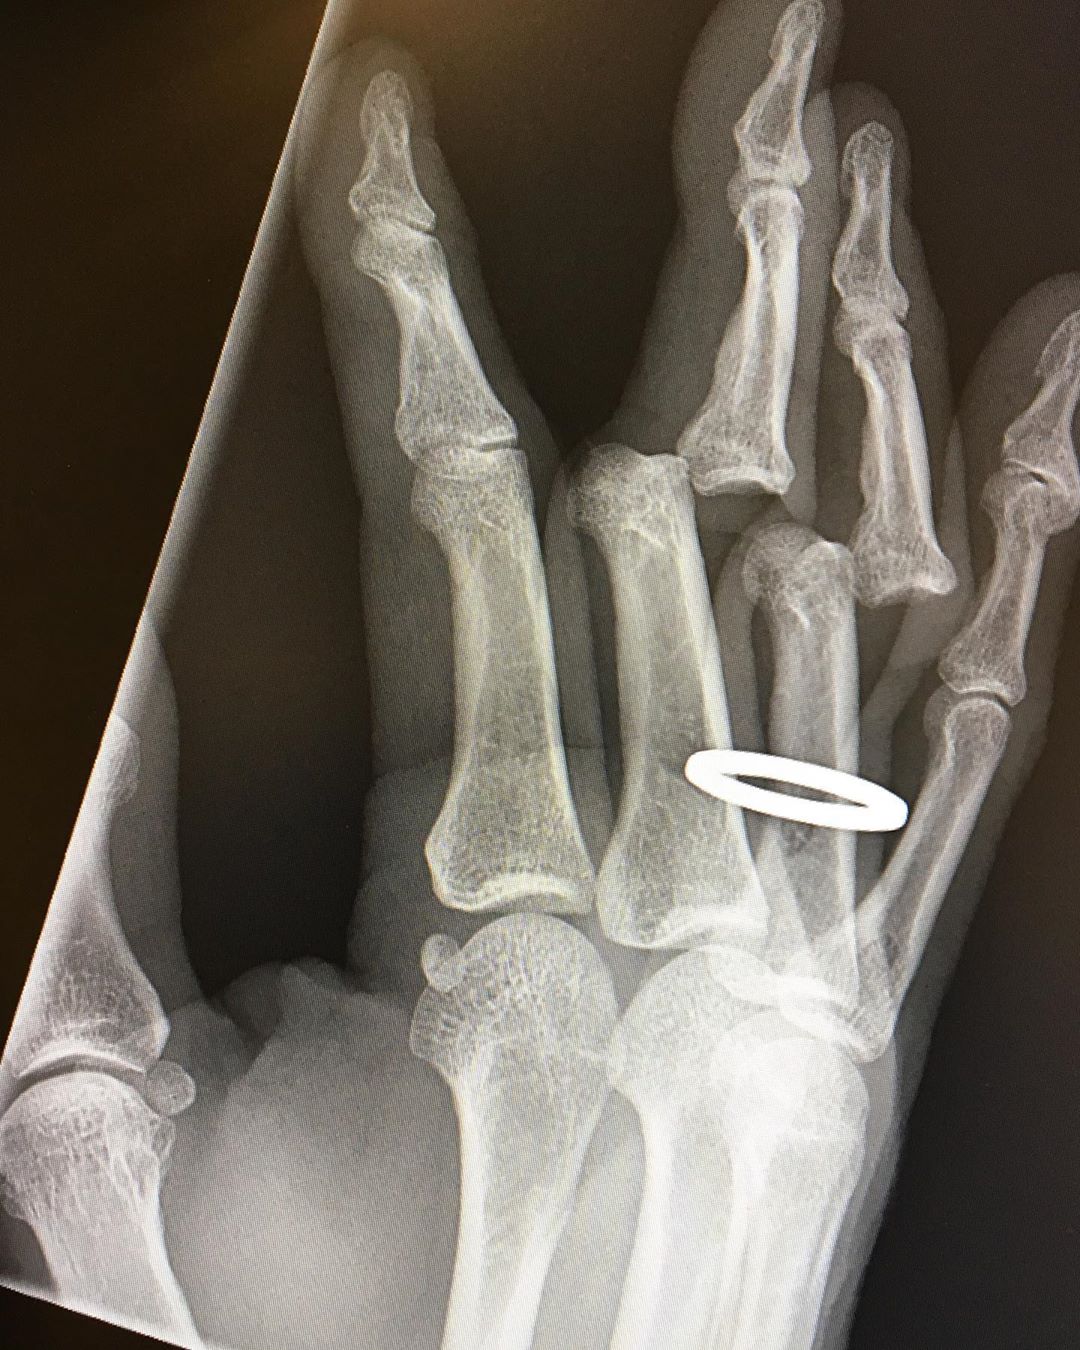

Hawk, tuvo que ir de urgencias a un centro médico para que le revisaran sus dedos fracturados y mostró las impactantes imágenes:

“Acabo de recibir mis radiografías. Tuvieron que cortarme el anillo antes de devolver mis huesos a su posición vertical. Todavía mis dedos están adoloridos, rígidos e hinchados, pero los puedo usar. Y todavía amo mi trabajo “.

Aquí las impactante imágenes: